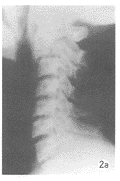

图2a X线片反映为C2椎弓根部骨折。

图2b MRI矢状位几乎无任何变化。